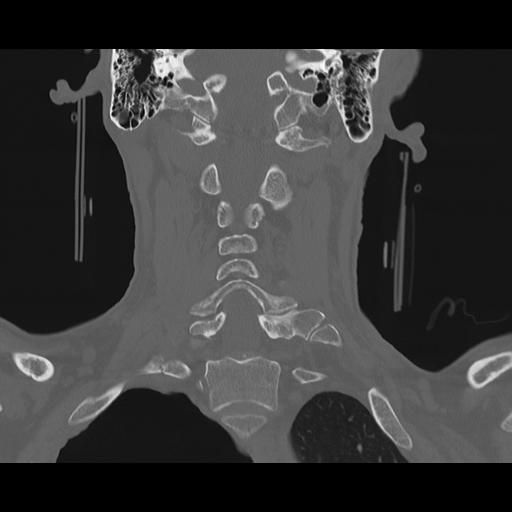

16 HUESO,,Coronal,2.000,HUESO,Coronal,